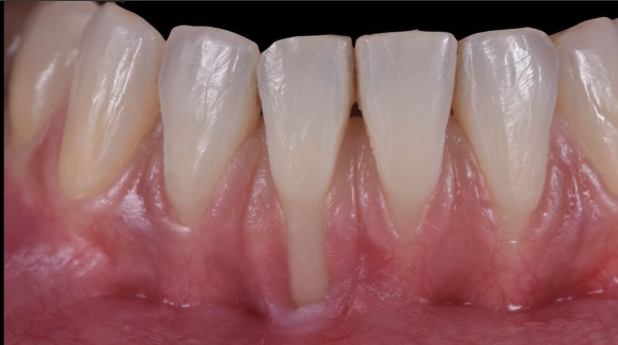

Questo è uno di quei casi: una serie di recessioni contigue, con caratteristiche molto diverse tra loro per profondità, spessore dei tessuti, ampiezza, quantità di tessuto cheratinizzato e morfologia delle papille. Una condizione che potremmo definire un “tricky defect”, proprio per la presenza simultanea di più elementi di difficoltà.

- Differente profondità delle recessioni tra gli elementi

- Disomogeneità nella distribuzione del tessuto cheratinizzato

- Biotipo sottile in alcuni siti, più spesso in altri

- Estetica compromessa e sensibilità diffusa